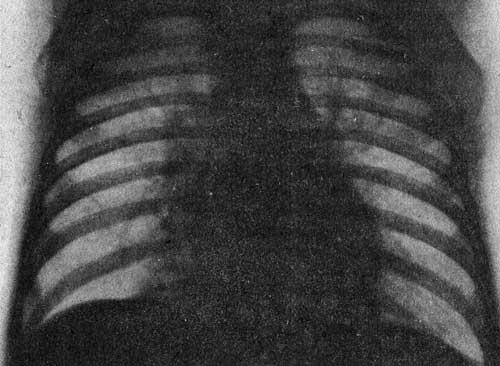

Двусторонняя пневмония, вызванная аденовирусной инфекцией